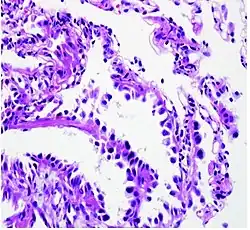

There are several factors that contribute to the transformation of normal alveolar epithelium into dysplastic, or pre-cancerous, lesions. Adenocarcinoma of the lung develops in a step-wise progression as type II pneumocytes undergo consecutive molecular changes that disrupt normal cell regulation and turnover. Atypical adenomatous hyperplasia (AAH) is considered a pre-cancerous lesion, and is thought to further progress to adenocarcinoma in situ and invasive adenocarcinoma of the lung. The lesions of AAH are <5 mm, can be single or multiple, and have a ground glass appearance on CT imaging. As more genetic mutations and dysregulation of normal cell signaling pathways accumulate, AAH can progress to adenocarcinoma in situ (AIS). AIS lesions are classified as small tumors <3 cm with abnormal type II pneumocyte cell growth that is limited to the alveolar spaces i.e. without invasion into the stroma, pleura, or vasculature. This type of growth is termed "lepidic" and is characteristic of adenocarcinoma of the lung in its earliest stages.[15]

Histopathology

If possible, a biopsy of any suspected lung tumor is performed to make a microscopic evaluation of the cells involved and is ultimately required to confirm diagnosis.[7] Biopsy should be attempted in distant lesions first to establish a histologic diagnosis and to simultaneously confirm metastatic staging. The biopsy material is also used to analyze whether the tumor express any specific mutations suitable for targeted therapy (e.g. EGFR mutation or ALK mutation). Biopsy can be accomplished via bronchoscopy, transthoracic needle biopsy, and video-assisted thorascopic surgery (VATS).[4]

While sputum cytology has been shown to have limited utility, thoracentesis, or aspiration of pleural fluid with an ultrasound-guided needle, should be performed when pleural effusion is present. When malignant cells are identified in the pleural aspirate of patients highly suspect for lung cancer, a definitive diagnosis and staging (stage IV adenocarcinoma of the lung) is established.[4]

Adenocarcinoma of the lung tends to stain mucin positive as it is derived from the mucus-producing glands of the lungs. Similar to other adenocarcinoma, if this tumor is well differentiated (low grade) it will resemble the normal glandular structure. Poorly differentiated adenocarcinoma will not resemble the normal glands (high grade) and will be detected by seeing that they stain positive for mucin (which the glands produce). Adenocarcinoma can also be distinguished by staining for TTF-1, a cell marker for adenocarcinoma.[29]

As discussed previously, the category of adenocarcinoma includes are range of subtypes, and any one tumor tends to be heterogeneous in composition. Several major subtypes are currently recognized by the World Health Organization (WHO)[1] and the International Association for the Study of Lung Cancer (IASLC) / American Thoracic Society (ATS) / European Respiratory Society (ERS):[30][31][32] lepidic predominant adenocarcinoma, acinar predominant adenocarcinoma, papillary predominant adenocarcinoma, micropapillary predominant adenocarcinoma, solid predominant adenocarcinoma, and solid predominant with mucin production. In as many as 80% of these tumors, components of more than one subtype will be recognized. Surgically resected tumors should be classified by comprehensive histological subtyping, describing patterns of involvement in increments of 5%. The predominant histologic subtype is then used to classify the tumor overall.[2] The predominant subtype is prognostic for survival after complete resection.[33]

To reveal the adenocarcinomatous lineage of the solid variant, demonstration of intracellular mucin production may be performed. Foci of squamous metaplasia and dysplasia may be present in the epithelium proximal to adenocarcinomas, but these are not the precursor lesions for this tumor. Rather, the precursor of peripheral adenocarcinomas has been termed atypical adenomatous hyperplasia (AAH).[10] Microscopically, AAH is a well-demarcated focus of epithelial proliferation, containing cuboidal to low-columnar cells resembling club cells or type II pneumocytes.[10] These demonstrate various degrees of cytologic atypia, including hyperchromasia, pleomorphism, prominent nucleoli.[10] However, the atypia is not to the extent as seen in frank adenocarcinomas.[10] Lesions of AAH are monoclonal, and they share many of the molecular aberrations (like KRAS mutations) that are associated with adenocarcinomas.[10]